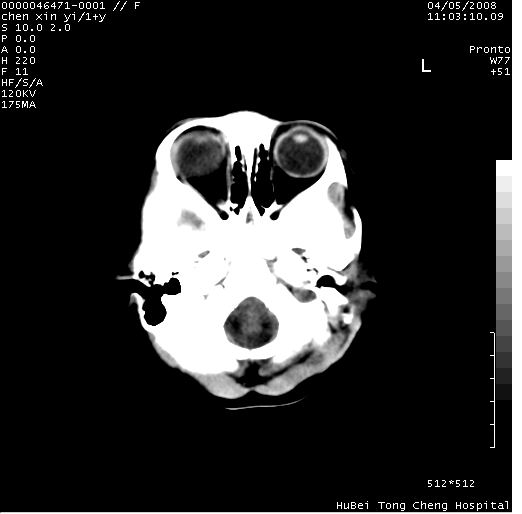

以下是引用zhangzhongshou在2008-4-9 12:54:00的发言:[br]请结合病史,有以下可能1、炎性肉芽肿钙化(含结核)2、寄生虫钙化(含脑囊虫)3、其他良性钙化性病变